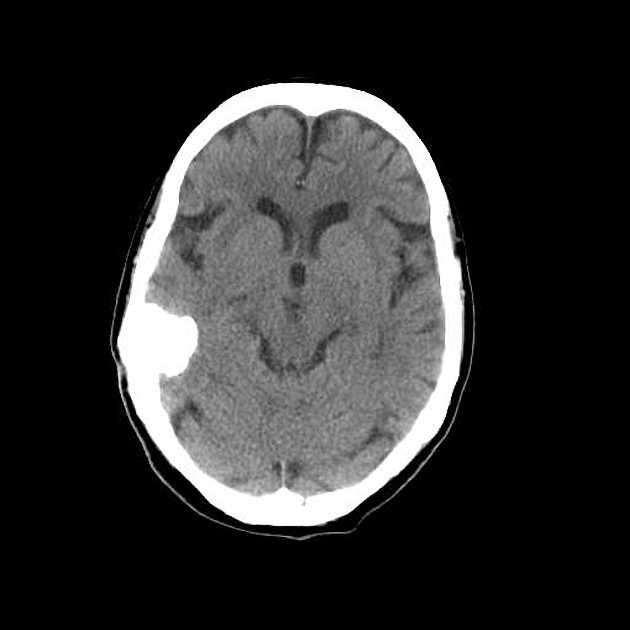

一名60岁的卡车司机出现了三个月的左灶性癫痫发作史。发作开始于左脚刺痛和麻木,累及下肢,然后发展为上肢。因此,他经历了左侧的强直阵挛性运动。癫痫发作的频率是每周一次。阵发性运动缺陷通常持续3至10天,然后完全恢复。神经系统检查显示轻度左痉挛性偏瘫(皮质功率为4/5)并伴有皮质感觉障碍。全部其他神经系统功能(包括眼底)均正常。血液,血清分析和X线胸片未显示任何异常。普通颅骨膜显示钙化(7x5厘米),在中央密集,在周围蓬松。CT显示右后壁钙化肿块,中心均匀密集,周围不均一。没有对比增强和脑水肿。在右侧位置进行顶叶开颅手术。硬脑膜浸润在右矢状旁区域的一小部分区域,但没有累及上覆骨。从邻近的内侧皮质表面解剖蛛网膜。这导致右顶叶通过重力自发地从肿瘤分离。因此,可以在没有任何脑部回缩的情况下完整切除肿瘤及其恶性肿瘤。

组织病理学检查显示钙化的脑膜瘤,富含砂砾样体,有小病灶,使人联想到脑膜上皮细胞。